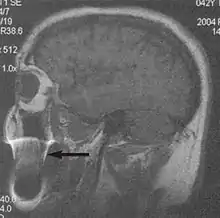

A motion artifact is one of the most common artifacts in MR imaging.[2] Motion can cause either ghost images or diffuse image noise in the phase-encoding direction. The reason for mainly affecting data sampling in the phase-encoding direction is the significant difference in the time of acquisition in the frequency- and phase-encoding directions.[1] Frequency-encoding sampling in all the rows of the matrix (128, 256 or 512) takes place during a single echo (milliseconds). Phase-encoded sampling takes several seconds, or even minutes, owing to the collection of all the k-space lines to enable Fourier analysis. Major physiological movements are of millisecond to seconds duration and thus too slow to affect frequency-encoded sampling, but they have a pronounced effect in the phase-encoding direction. Periodic movements such as cardiac movement and blood vessel or CSF pulsation cause ghost images, while non-periodic movement causes diffuse image noise (Fig. 1). Ghost image intensity increases with amplitude of movement and the signal intensity from the moving tissue. Several methods can be used to reduce motion artifacts, including patient immobilisation, cardiac and respiratory gating, signal suppression of the tissue causing the artifact, choosing the shorter dimension of the matrix as the phase-encoding direction, view-ordering or phase-reordering methods and swapping phase and frequency-encoding directions to move the artifact out of the field of interest.[1]

Flow can manifest as either an altered intravascular signal (flow enhancement or flow-related signal loss), or as flow-related artifacts (ghost images or spatial misregistration). Flow enhancement, also known as inflow effect, is caused by fully magnetised protons entering the imaged slice while the stationary protons have not fully regained their magnetization.[1] The fully magnetized protons yield a high signal in comparison with the rest of the surroundings. High velocity flow causes the protons entering the image to be removed from it by the time the 180-degree pulse is administered. The effect is that these protons do not contribute to the echo and are registered as a signal void or flow-related signal loss (Fig. 2).[1] Spatial misregistration manifests as displacement of an intravascular signal owing to position encoding of a voxel in the phase direction preceding frequency encoding by time TE/2.The intensity of the artifact is dependent on the signal intensity from the vessel, and is less apparent with increased TE.[1]